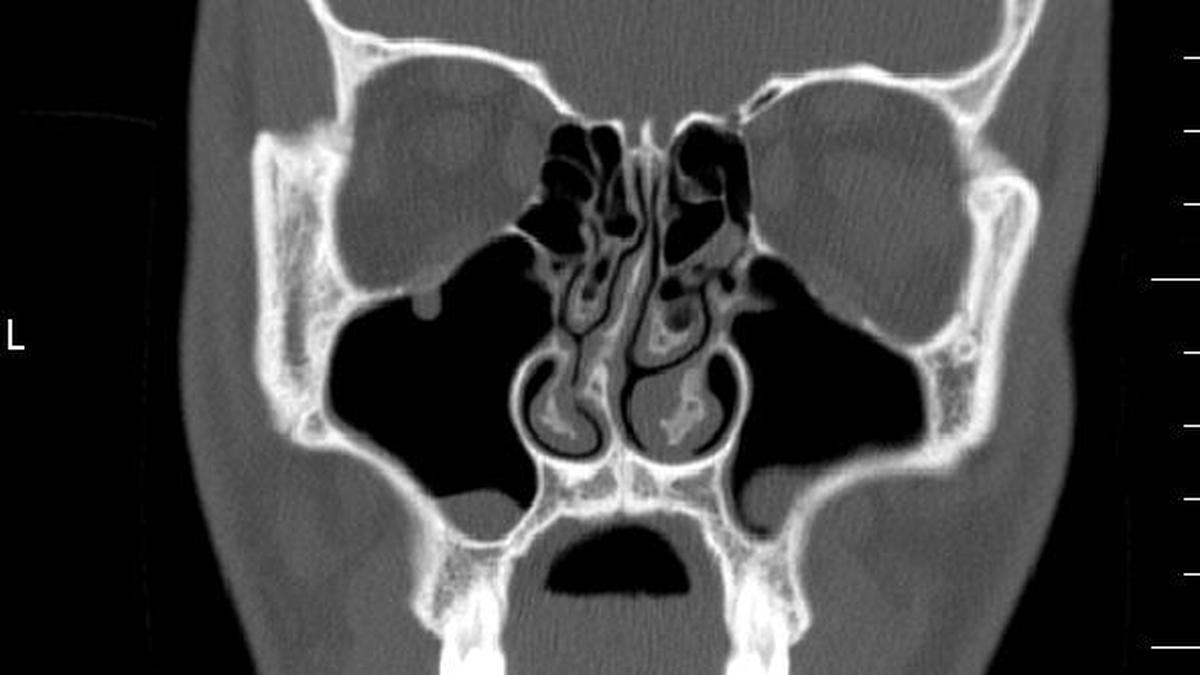

Deviated septum: why a bent nasal wall is more common than you think and when to seek treatment Premium